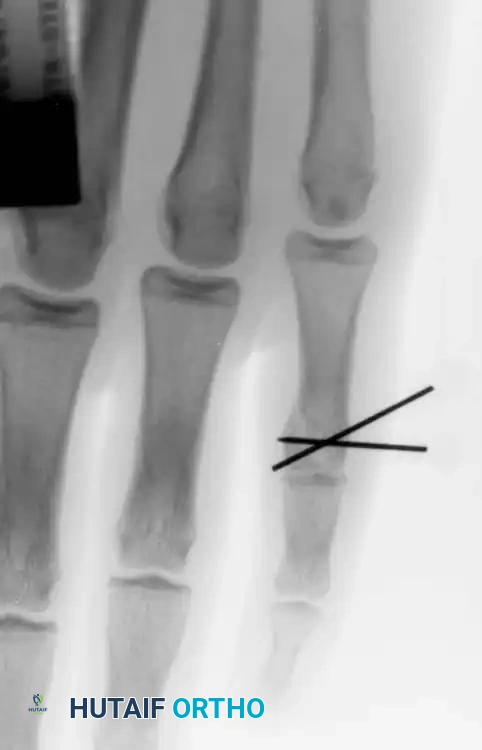

Fig. 64-71 Malunited fracture of fifth metacarpal neck treated by open reduction and fixation with one Kirschner wire inserted obliquely. This rarely is necessary because normal motion of fifth carpometacarpal joint permits tolerance of 40 degrees of angulation at fracture site.